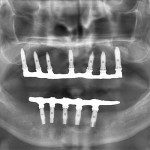

Realizado em: Agosto de 2012Detalhes do tratamento: Implantes instalados imediatamente após extrações de dentes inferiores e prótese fixa sobre implantes (instalada 72 horas após a cirurgia).

Fiz tratamento odontológico com Dr. Alexandre e Dra. Mariza. Foi muito bom, gostei muito e estou muito satisfeita. Com Dr. Alexandre fiz cirurgia e implante. Foi muito bom não sentir dor, foi perfeito. Com Dra. Mariza fiz prótese fixa sobre implante inferior e prótese total “normal” superior. Estou muito satisfeita com o trabalho deles!